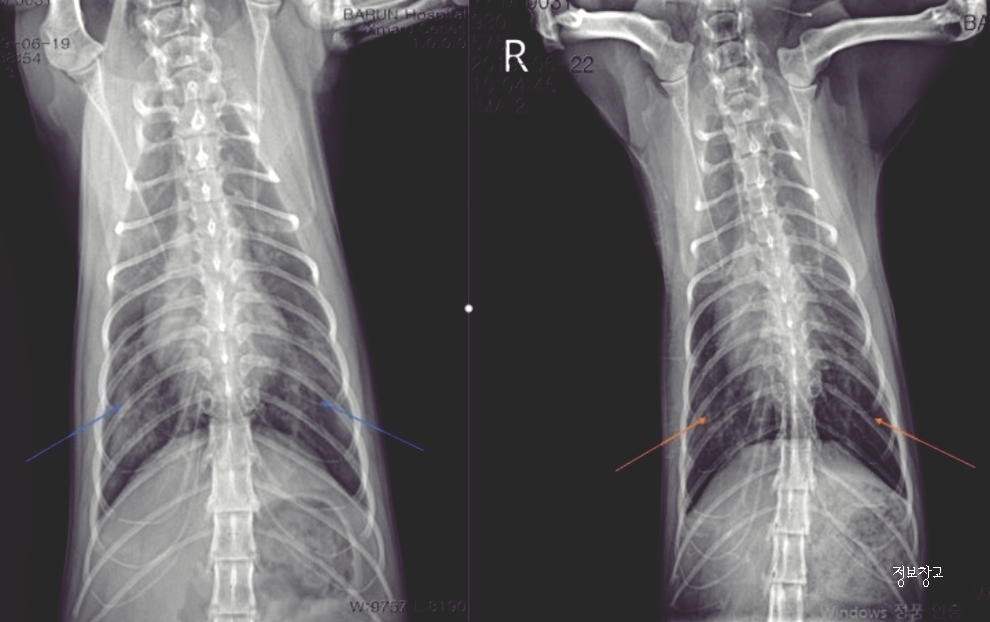

② 고양이 천식

특징

- 낮게 엎드린 자세

- 목을 길게 빼고 ‘흡흡’ 소리

- 숨이 가쁜 느낌

🚨 주의

- 만성 질환

- 방치 시 호흡 곤란 위험

👉 반복되면 반드시 병원 진단 필요

⑤ 심장 질환

- 잦은 기침

- 숨 가쁨

- 쉽게 지침

🚨 위험 신호

- 노령묘

- 갑작스런 기침 증가

👉 심장 문제는 조기 진단이 매우 중요합니다.

⑥ 폐렴·흉강 문제

- 기침 + 무기력

- 호흡 소리 거침

- 식욕 저하

🚨 응급 가능성

- 즉시 병원 진료 필요